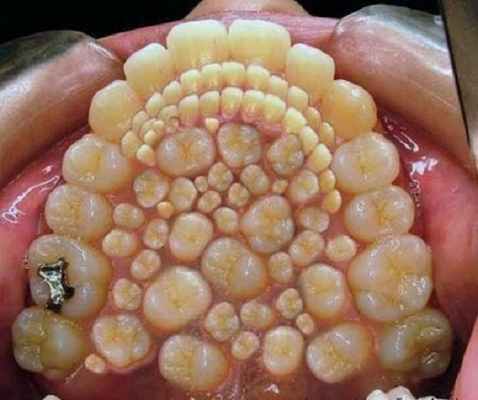

«Лишние зубы» или полиодонтия…

Полиодонтия – это аномальное количество зубов.

В медицине это заболевание часто называют гипердонтией, а «лишние» зубные элементы – сверхкомплектными зубами. До сих пор проводятся исследования, почему возникает такая патология. Большинство ученых связывает ее с нарушениями при закладке зубных зачатков.

Природой предусмотрено, чтобы за жизнь у человека вырастало не больше 20 молочных и 32 постоянных зубов, но случаются исключения, причем в наше время довольно часто. По статистике, в среднем аномалия зубов встречается у 2% населения планеты, чаще всего у мужчин.

Только в 2014 году было проведено две операции, в одной из которых удалили 80, а в другой – рекордные 232 зуба. До этого времени максимальная цифра составляла 37 зубов.

Самой распространенной гипердонтией (аномалией числа зубов) является аномалия верхних резцов. Реже встречаются сверхкомплектные зубы среди нижних резцов и в других частях челюсти. Они могут быть самых разнообразных форм и размеров. Обычно это небольшие зубы в форме конуса.

Формирование лишних зубов сегодня встречается достаточно часто. По статистике у 70% больных появляется всего один лишний резец, в 25% случаев – 2 свJерхкомплектных элемента, и только у 5% всех пациентов при обследовании находят 3 и больше зубов.

Самое распространенное место, где появляется полиодонтия, – средние верхние резцы, а также моляры, премоляры и клыки. Намного реже эта проблема поражает нижнюю челюсть. Лишние зубы могут появиться на зубной дуге, а также в области верхнего неба или в преддверии полости рта.

Как выглядит полиодонтия

Также в медицинской практике известны случаи, когда полиодонтия была скрытой и обнаруживалась только при рентгенографии. Существует множество разных случаев аномального развития числа зубов, и если вы заметили симптомы, то обязательно необходимо обратиться в стоматологию.